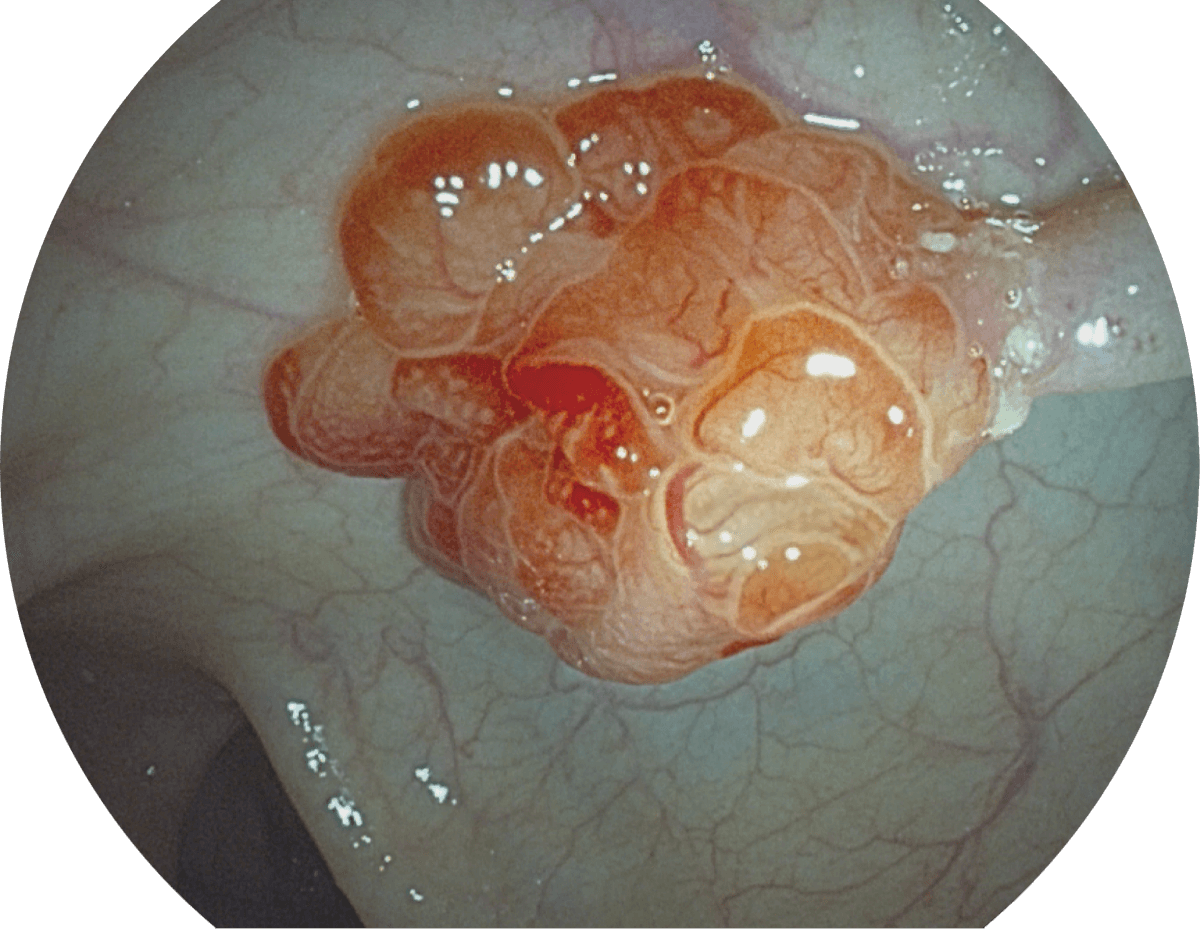

具有聚谱成像技术(SFI)及光电复合染色成像技术(VIST),可完美呈现粘膜细节及病变特征。

WL